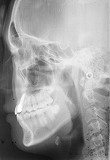

症例

歯列矯正 歯肉形態修正手術 インプラント メタルボンドを併用した症例です。

この治療では1本の歯も削ったり、抜いたりはしていません。

- 先天的に上顎側歯列が欠如している患者さんです。

- はじめに矯正治療を行い、本来歯があるべき位置に矯正して、インプラント手術のためのスペースを確保しました。